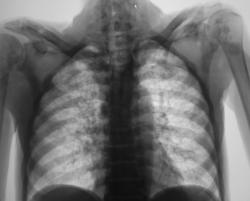

Синдром диссеминации.

Диссеминированный туберкулёз лёгких.

Милиарная диссеминация, преимущественно в средних и нижних отделах.

Случай представлен доктором Коробейниковым.